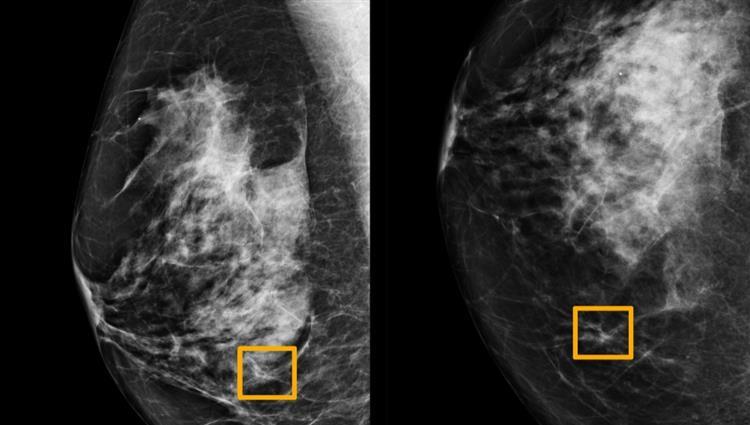

تمكنت جوجل من تطوير ذكاء اصطناعيا جديدا من خلال شركة DeepMind التابعة لها، يمكنه اكتشاف سرطان الثدى بدقة أكثر من الأطباء، وهو أكثر أنواع السرطان شيوعًا بين النساء، إلا أن الكشف عنه صعب نظرًا لارتفاع معدلات النتائج الإيجابية الخاطئة، فيعطى تصوير الماموجرام نتائج إيجابية تجاه المرض حتى فى حالة عدم وجود سرطان، ما يؤدى إلى تدخلات طبية غير ضرورية.

ووفقا لما ذكره موقع “engadget” الأمريكى طورت DeepMind نموذج الذكاء الاصطناعى، الذى يمكنه التعرف على سرطان الثدى من خلال المسح الضوئى بنتائج أكثر دقة، حيث دربت الذكاء الاصطناعى الخاص بها باستخدام بيانات كبيرة من المرضى فى كل من الولايات المتحدة والمملكة المتحدة.

وأظهرت أنها يمكن أن تقلل من النتائج الإيجابية الخاطئة بنسبة 5.7%، وكذلك النتائج السلبية الكاذبة بنسبة 9.4% فى الولايات المتحدة.

فيما حدث انخفاض للنتائج الخاطئة فى الكشف عن سرطان الثدى فى المملكة المتحدة بنسب أقل من 1.2 % و 2.7% على التوالي في المملكة المتحدة، ما يشير إلى أن نظام الكشف الحالي في الولايات المتحدة أقل دقة من نظام المملكة المتحدة الحالي.